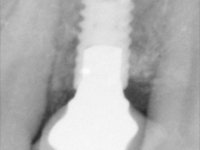

• Placement of an implant at the tooth site 2.2. Rehabilitation of the implant with a coronary and gingival component abutment. in which the screw access hole was "camouflaged" with a feldspathic veneer.

Treatment began with re-preparation of the cast post and core, with the purpose of placing the cervical finishing lines with an intra-sulcular location and simultaneously making a suitable temporary crown. With a very simple orthodontic treatment, the diastema was closed between the upper central incisors, and this position was stabilized with a wire placed on the palatal surface of the central, functioning as containment. Later, a slow orthodontic traction of tooth 2.2 was attempted, in order to reduce, although very slightly, the vertical bone loss in this area. At the end of the traction, tooth 2.2 was extracted and the area was provisionally rehabilitated with a composite resin crown bonded to the adjacent teeth. A dental implant was placed in the area of tooth 2.2 and the temporary crown was again bonded to resin, provisionally rehabilitating the patient during osseointegration. In tooth 1.3 a gingivectomy with an electric scalpel was performed, with the intention of raising the cervical level of 1.3 achieving greater harmony with tooth 2.3. Stabilized soft tissues were impressed using the open tray technique with putty and light addition silicones. Collection of the color of both the dental component and soft tissues was done by the ceramist in the office. In the laboratory, the impressions were transferred to plaster and gave origin to work models that were properly analyzed. It was decided to assemble a metal-ceramic abutment screwed onto the implant. This abutment was cast with a noble alloy and subsequently coated with coronary and gingival ceramics. Due to the inclination of the implant, the screwing inevitably conditioned the exit of the screw hole through the vestibular surface. In order to conceal this situation, the design of the abutment has already been conceived with the intention of accommodating on the vestibular surface the bonding of a feldspathic veneer. This abutment was tested in the mouth and adjustments were made in the gingival ceramic component. Its adaptation to the soft tissues was done in a subtractive way, with a drill, as well as additive, adding resin composed of gingival tonality.